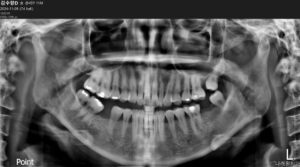

정밀한 검사를 위해

파노라마 사진을 촬영해 보았는데요.

아래턱 왼쪽 두 번째 큰 어금니(#37)와

오른쪽 첫 번째 큰 어금니(#46)가

상실된 상태였으며,

위턱 왼쪽 두 번째 큰 어금니(#27)도

상실되어 있었는데요.

다행히 상실된 부위의 양측 치아가

빈 공간으로 많이 기울어졌거나

맞물리는 치아가

내려와 있지 않은 상태였기 때문에

충분히 임플란트를 식립 할 공간이

있는 상황이었습니다.